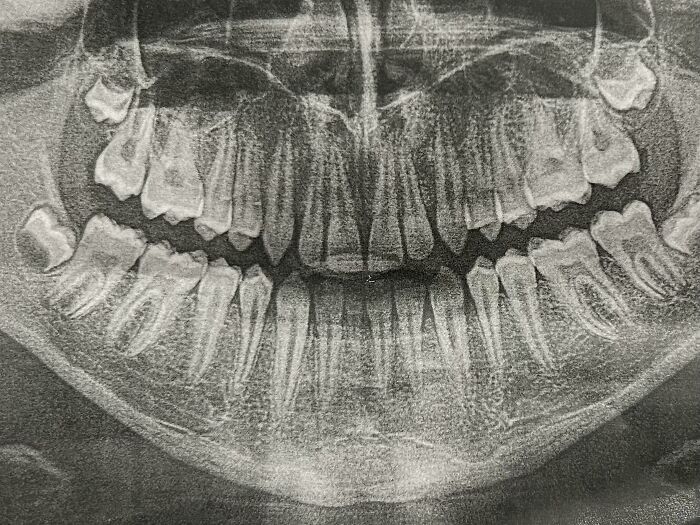

#24 I Have 7 Wisdom Teeth

Image credits: dredgeops